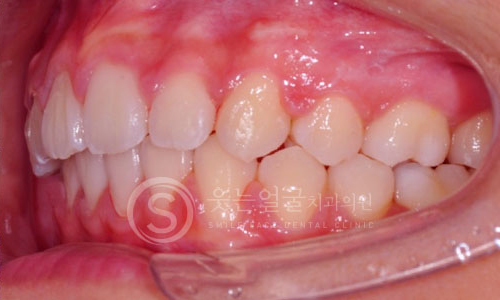

한눈에 보는

치아교정 전후사진